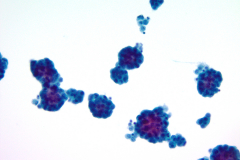

Immunohistochemistry (IHC) stains can also be an important tool in proper diagnosis of EHE. Stains such as CD31, CD34, and ERG have been described to stain EHE.2,3 CD31 is a platelet endothelial cell marker expressed frequently in vascular endothelial cells. CD34 stains for 90% of vascular tumors because it is a highly glycosylated transmembrane glycoprotein associated with the origin of vascular tumors. Positive staining for both CD31 and CD34 is considered diagnostic of this tumor.1 In this case, we have CAMTA1, a tumor suppressor transcription factor, staining positively for EHE shown in Image 1.